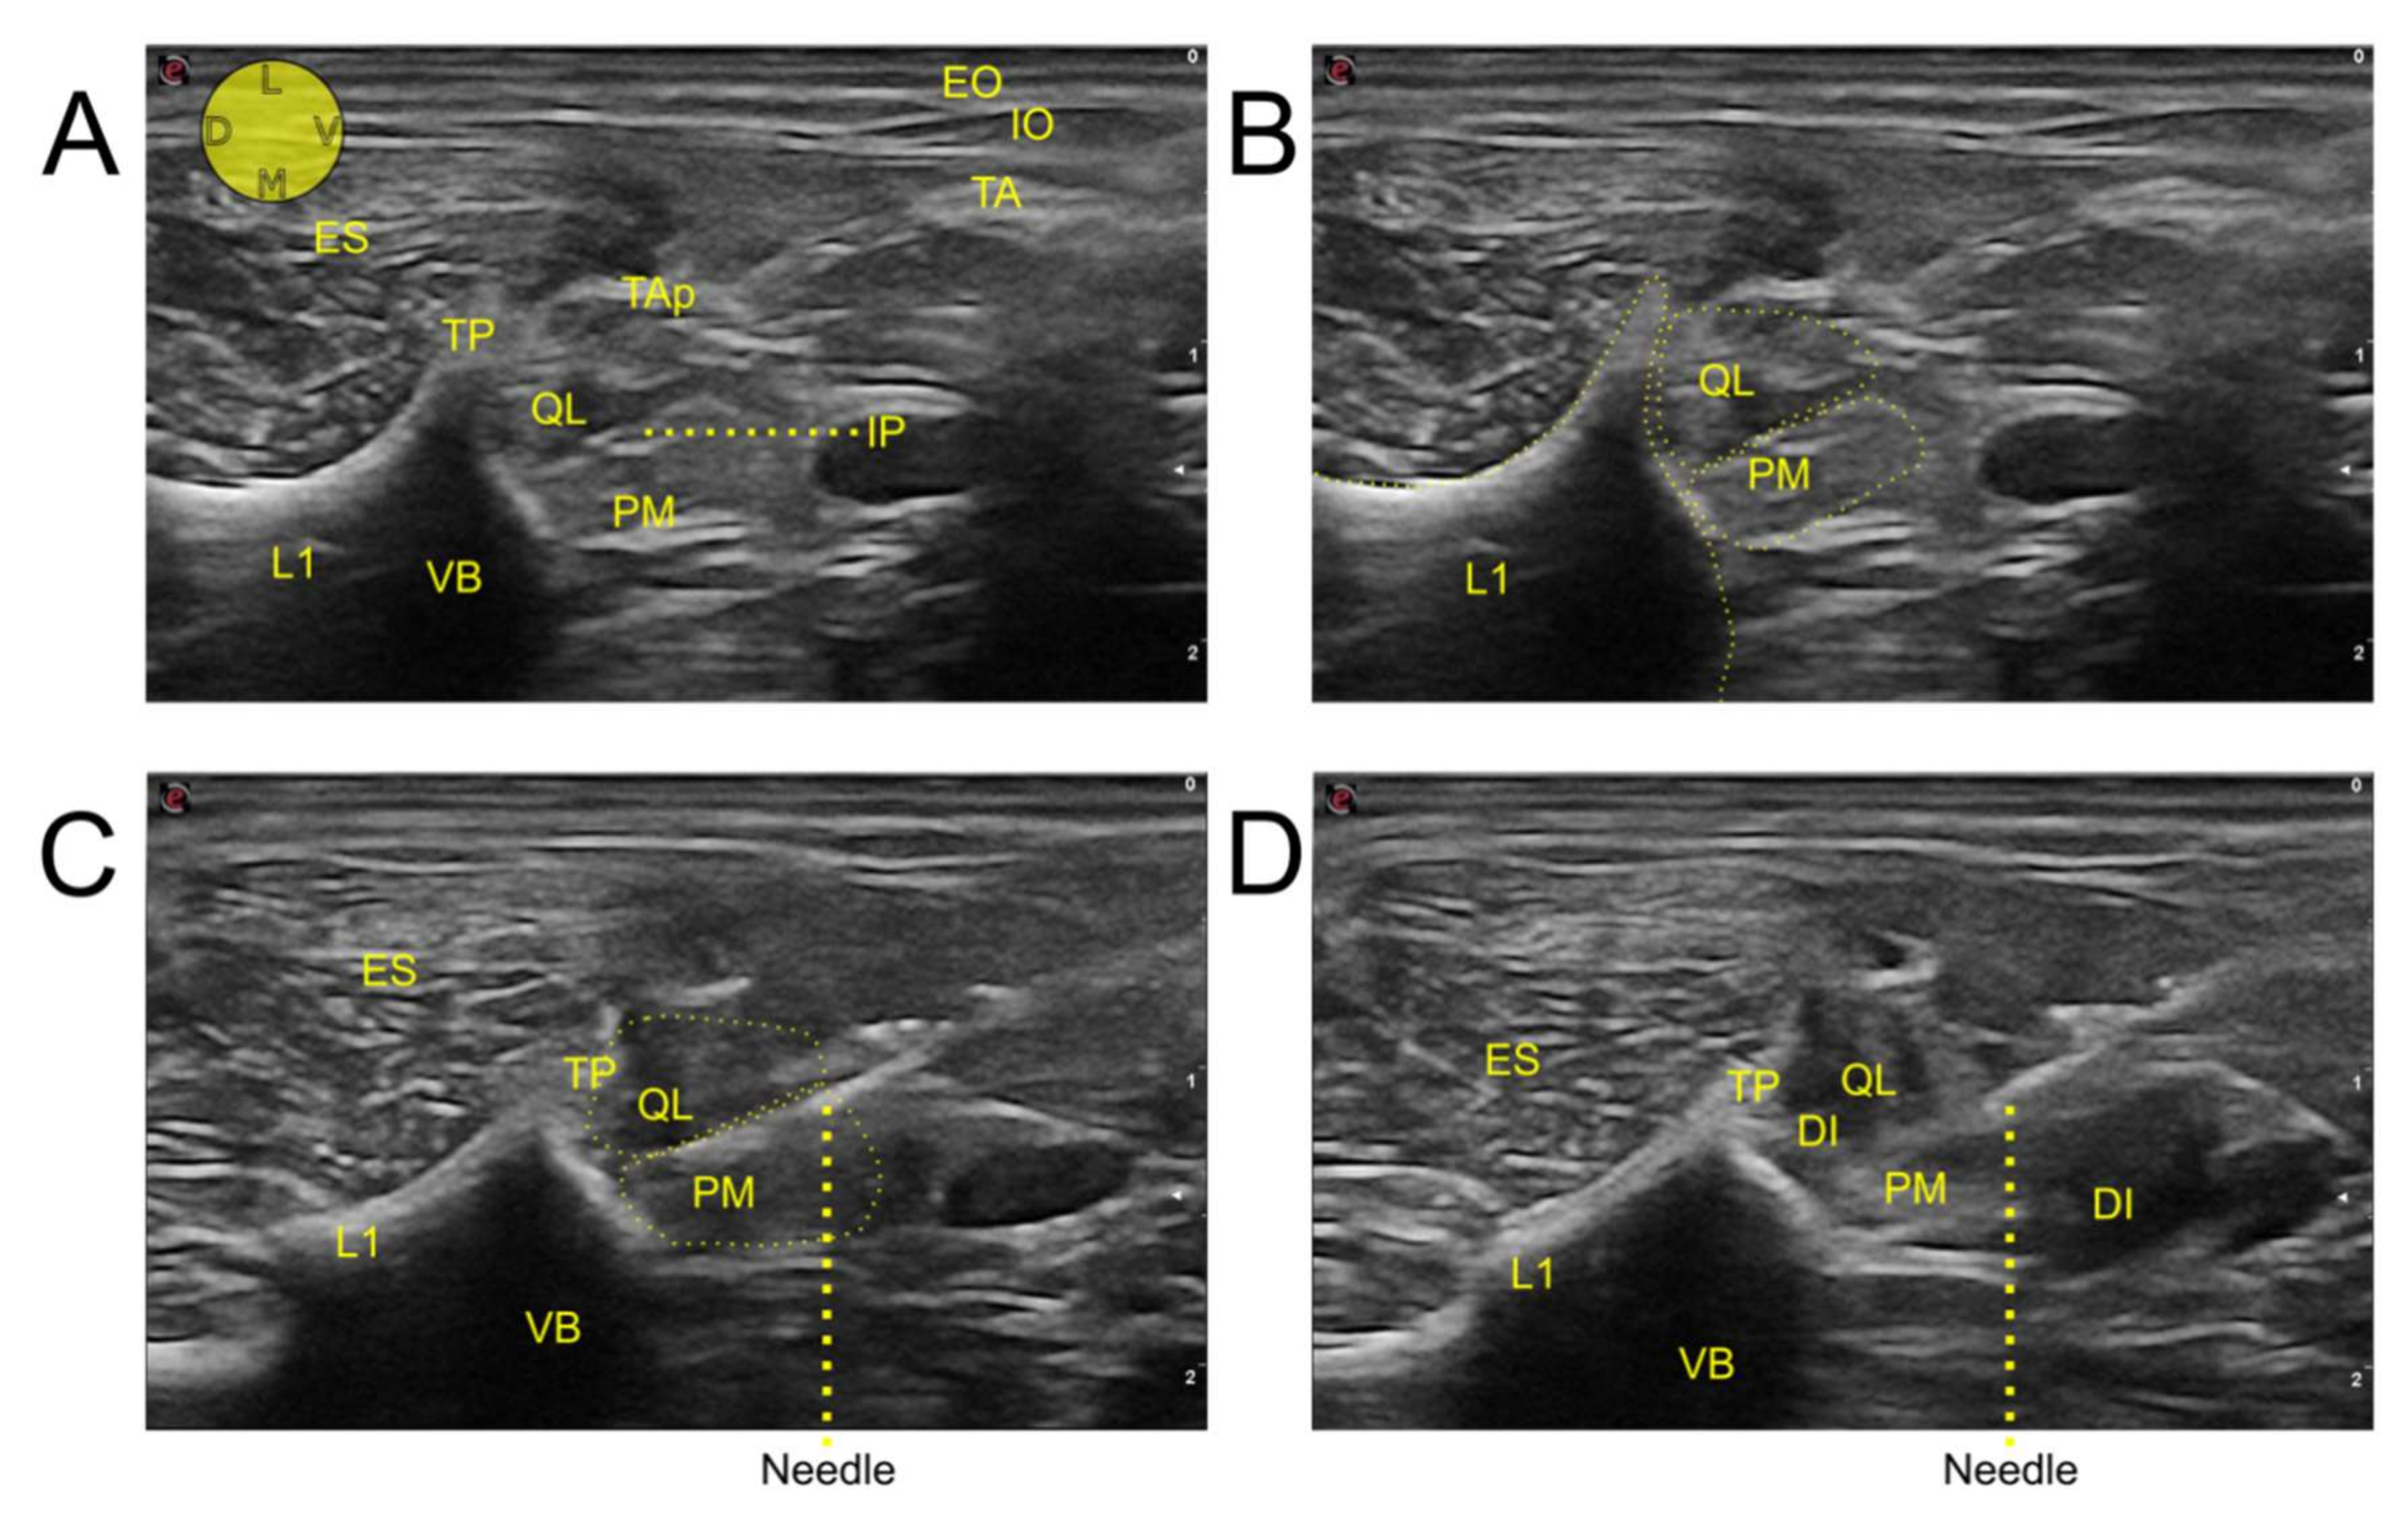

2.1. Ultrasound-Guided Injection Technique

3.2. Injection Technique